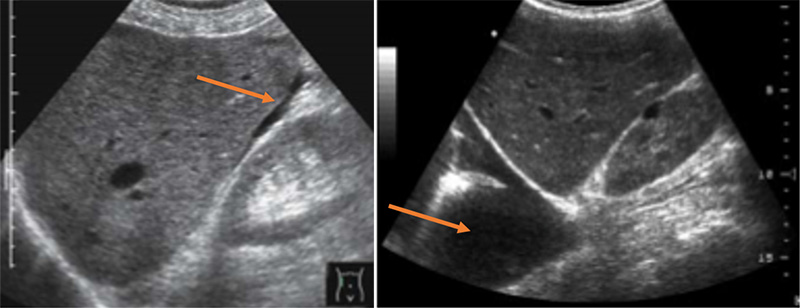

Figures 58A & B. Fluid third-spacing in severe dengue demonstrated via views of free fluid (arrow) in Morrison’s pouch (A), the pleural space (arrow) (B). (Courtesy of Dr. Elijah Katz, Medicines Sans Frontieres)

Figure 58C. Fluid third-spacing in severe dengue demonstrated via view of free fluid (arrow) in the pericardium.

- Plasma leakage and third spacing

- Ascites

- Pleural effusions

- Pericardial effusion

- All tend to develop during “critical”

- Effusions and ascites are markers of more severe disease.54,55